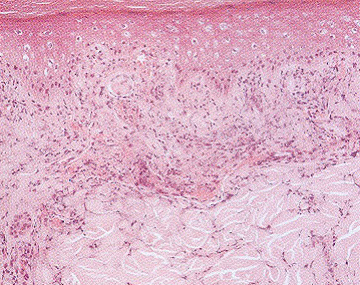

Despite the negative results of the immune markers, vasculitis was thought to be the most likely underlying cause of his illness and he was commenced on intravenous hydrocortisone at a dose of 100 mg 6-hourly. Intravenous septrin was also commenced to cover the possibility of an undiagnosed nocardia lung abscess. ANCA was repeated prior to recommencement of steroids and the repeat test was now positive for C-ANCA at a titre of 1:160 with an anti..PR3 of >200RU/ml. He also developed a vasculitic lesion on his right big toe. Biopsy of the lesion confinned a leucocytoclastic vasculitis (Fig 4). A diagnosis of Wegener’s granulomatosis was therefore made on the basis of the presence of nasopharyngeal ulcers, lung nodules, episcleritis. vasculitic skin lesions and +ve C-ANCA/PR-3.